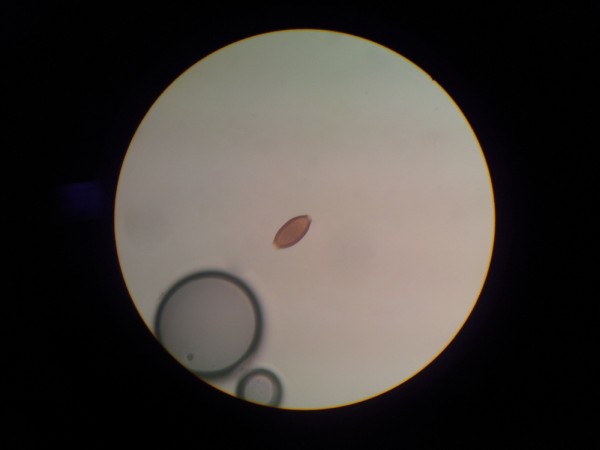

При микроскопии кала можно обнаружить следы крови и значительное количество слизи. Если поражение кишечника выражено, в кале могут быть найдены яйца червя.

Трихоцефалёз — это инфекция, вызванная нематодой (червём) Trichuris trichiura. Симптомы могут включать абдоминальные боли, диарею, а при тяжелых инфекциях — анемию и истощение. Диагностика основывается на обнаружении яиц в стуле.